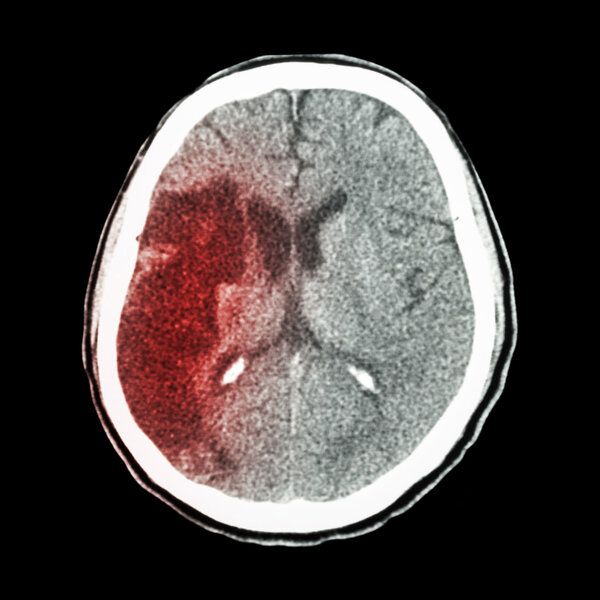

目前,我國平均每10秒就有1人初發(fā)或復(fù)發(fā)腦卒中,每28秒就有1人因腦卒中離世;幸存者中,約40%重度殘疾,90%存在運(yùn)動障礙。

年近六旬的蘇女士是一名退休教師,四年前,她突發(fā)左側(cè)肢體無力,被緊急送至當(dāng)?shù)蒯t(yī)院救治,被診斷為急性缺血性腦卒中,立即急診行介入治療。不幸的是,蘇女士術(shù)后仍遺留了左側(cè)肢體運(yùn)動功能障礙問題。四年多來,盡管患者及家屬積極配合進(jìn)行康復(fù)治療,但左側(cè)肢體運(yùn)動功能障礙問題并沒有顯著改善。